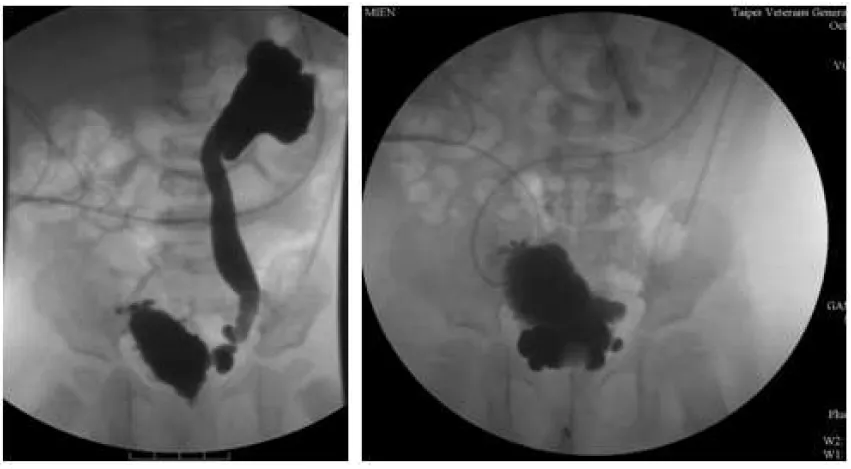

【109-1 醫學(四) 第17題】6個月大男嬰因泌尿道感染合併敗血症,之後安排VCUG(Voiding cystourethrogram)檢查結果如附圖。下列敘述何者錯誤?

詳解

破題關鍵

這張VCUG影像顯示嬰兒有嚴重的膀胱輸尿管逆流(VUR),造影劑從膀胱逆流至腎臟,且輸尿管和腎盂腎盞有明顯擴張。對於嬰幼兒的高級別VUR,雖然有腎臟受損風險,但通常不會「立即」進行手術矯正,而是會先考慮藥物治療及觀察,並排除其他潛在病因。因此,「立即接受手術矯正治療」的說法是錯誤的。